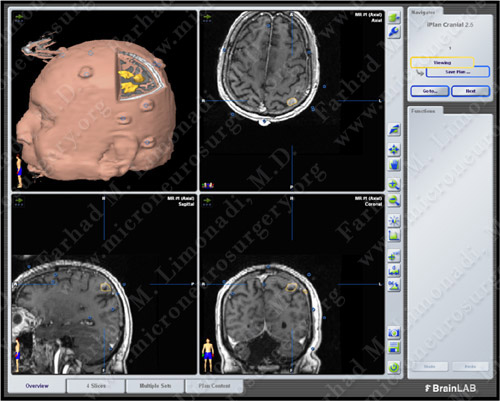

Computer Navigation

Computer navigation and stereotaxy utilized to map and localize the tumors (outlined in yellow) during surgery.

Utilizing computer navigation, a small craniotomy was performed precisely over both tumors and both tumors were removed using this small opening.